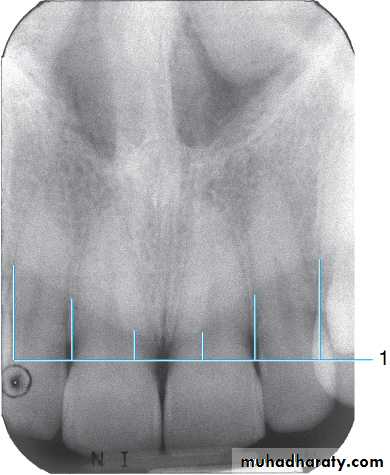

Radiograph of the mandibular midline area. This radiograph shows the (1) mental ridge, (2) nutrient canal, (3) nutrient foramen, (4) genial tubercles surrounding the (5) lingual foramen, and (6) inferior (lower) border of the mandible (radiopaque band of dense cortical bone).

*Often times when the vertical angulation is too excessive- you see the cortical bone